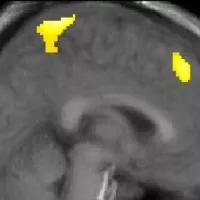

“It certainly didn’t arise from trying to find an application for interactive whiteboards.” says Howard-Jones. “It actually arose from the nucleus accumbens (the NAcc, a knot of neurons important in reward, pleasure, addiction, aggression and fear) and realising we’d missed a big trick in education, in that we have an overly simple idea of the relationship between reward and learning.”

The background to this is dopamine. This chemical is present in the brain and the speed of uptake is proportional to, Howard-Jones explains, the amount you desire something. Dopamine helps orient your attention, but it also enhances synaptoplasticity – that is, how easy it is to learn something. The more you desire something, as measured by dopamine uptake, the more you remember.

Video games are hugely desirable – on a level with amphetamines. “You can see what’s happening with the help of our new neuro-imaging tech,” says Dr Howard-Jones “and it’s very clear that the reward is being very, very stimulated (by video games). What’s clear is that when the rewards system is stimulated your efficiency of learning improves.” And nothing stimulates the rewards system like video games.